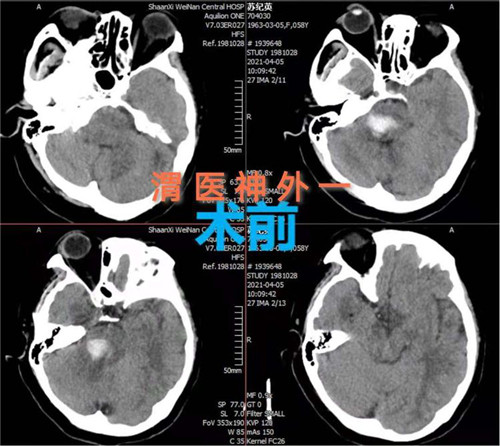

4月5日,市中心医院神经外科一病区通过开颅手术成功救治一例脑干出血患者。该手术的实施和成功填补渭南市该项领域空白,达到省级先进水平。

患者女性,58岁,突然意识不清3小时,行头颅CT检查提示:脑干出血。入院时患者深度昏迷,GCS评分6分。患者脑出血部位特殊,病情危重,手术风险大,并且既往有高血压、糖尿病史,围手术期随时有死亡可能。神经外科一病区赵金安主任带领团队评估手术风险,立刻上报医院,并和家属及时沟通,经反复讨论后最后决定实施开颅脑干血肿清除术:一级入路为右侧乙状窦后入路;二级入路为三叉神经下一面听神经上脑桥侧安全区。